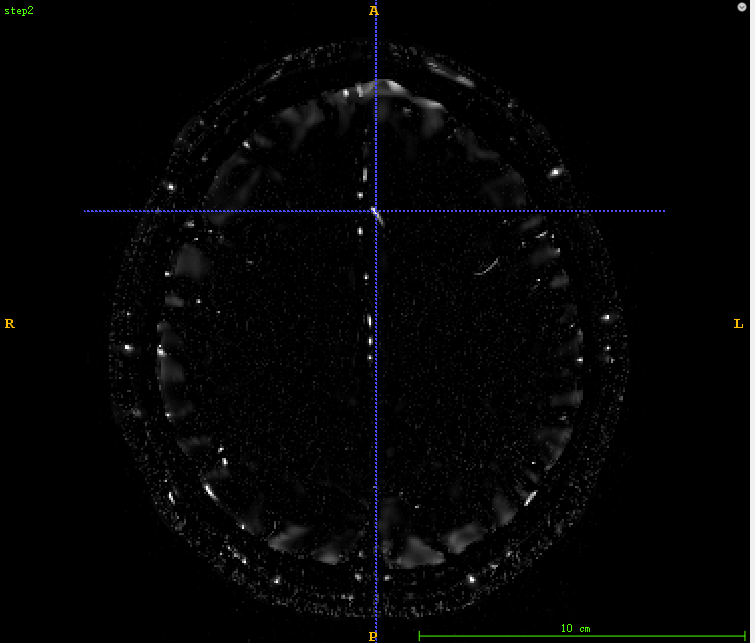

4、血管分割代码详解

4.1、采用itk的多尺度海森矩阵血管增强

4.2、 将增强后的血管归一化到0-255范围

4.3、 对归一化的血管进行固定阈值分割

代码:

def vessleSegment(pathDicom): sigma_minimum = 0.2 sigma_maximum = 3. number_of_sigma_steps = 8 lowerThreshold = 40 output_image = 'vessel.mha' input_image = itk.imread(pathDicom, itk.F) # 1 ImageType = type(input_image) Dimension = input_image.GetImageDimension() HessianPixelType = itk.SymmetricSecondRankTensor[itk.D, Dimension] HessianImageType = itk.Image[HessianPixelType, Dimension] objectness_filter = itk.HessianToObjectnessMeasureImageFilter[HessianImageType, ImageType].New() objectness_filter.SetBrightObject(True) objectness_filter.SetScaleObjectnessMeasure(True) objectness_filter.SetAlpha(0.5) objectness_filter.SetBeta(1.0) objectness_filter.SetGamma(5.0) multi_scale_filter = itk.MultiScaleHessianBasedMeasureImageFilter[ImageType, HessianImageType, ImageType].New() multi_scale_filter.SetInput(input_image) multi_scale_filter.SetHessianToMeasureFilter(objectness_filter) multi_scale_filter.SetSigmaStepMethodToLogarithmic() multi_scale_filter.SetSigmaMinimum(sigma_minimum) multi_scale_filter.SetSigmaMaximum(sigma_maximum) multi_scale_filter.SetNumberOfSigmaSteps(number_of_sigma_steps) itk.imwrite(multi_scale_filter.GetOutput(), "step1.mha") # 2 OutputPixelType = itk.UC OutputImageType = itk.Image[OutputPixelType, Dimension] rescale_filter = itk.RescaleIntensityImageFilter[ImageType, OutputImageType].New() rescale_filter.SetInput(multi_scale_filter) itk.imwrite(rescale_filter.GetOutput(), "step2.mha") # 3 thresholdFilter = itk.BinaryThresholdImageFilter[OutputImageType, OutputImageType].New() thresholdFilter.SetInput(rescale_filter.GetOutput()) thresholdFilter.SetLowerThreshold(lowerThreshold) thresholdFilter.SetUpperThreshold(255) thresholdFilter.SetOutsideValue(0) thresholdFilter.SetInsideValue(255) itk.imwrite(thresholdFilter.GetOutput(), "step3.mha")